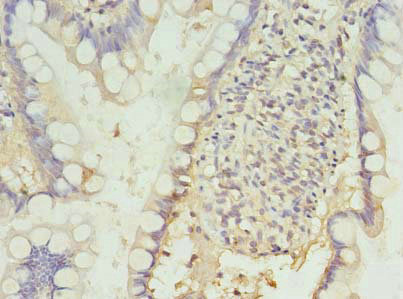

Immunohistochemistry of paraffin-embedded human small intestine tissue using CSB-PA619964LA01HU at dilution of 1:100